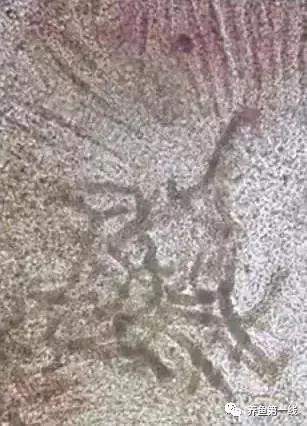

1.鳃丝上的黑色素细胞在显微镜下一般呈类似 雪花一样的星芒 状,树突状分支很多(见下图):

(低倍镜下鳃丝上的黑色素细胞)

(高倍镜下鳃丝上的黑色素细胞)